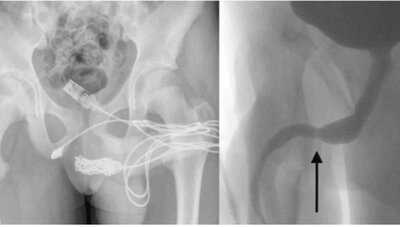

डॉक्टरों को यू उसके प्राइवेट पार्ट में से यूएसबी निकालने के लिए ऑपरेशन करना पड़ा। युवक के पेनीस के पास ही एक बड़ा चीरा लगाने के बाद केवल को निकाला जा सका। इसके लिए डॉक्टरों ने पहले युवक के प्राइवेट पार्ट का सिटी स्कैन किया जिसमें उन्हें यूएसबी केबल अंदर फंसे हुए नजर आए डॉक्टर के पास चीरा करके केबल को निकालने के अलावा कोई दूसरा रास्ता नहीं था इसलिए ऑपरेशन करना पड़ा। ऑपरेशन सफल होने के बाद डॉक्टर ने बताया कि युवक को छुट्टी दे दी गई है और उन्हें कोई अंदरूनी चोट तो नजर नहीं आई लेकिन दो सप्ताह बाद वापस युवक को स्कैनिंग के लिए आना पड़ेगा।